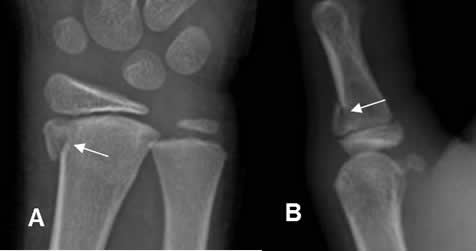

Fig 74 A. Salter tipo III.

A y B: Rx AP. Fracturas verticales en las epífisis del radio y el dedo, por lesiones tipo III.